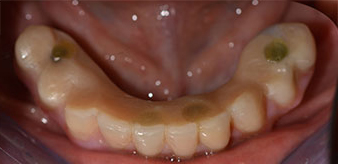

The 64-year-old patient presented with residual dentition of teeth 38, 33 and 43 and a clasp denture in the mandible (Fig. 1 and 2).

residual dentition

Fig. 1

Fig. 2